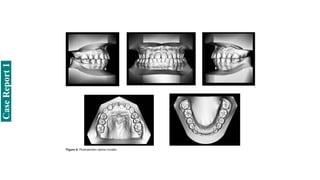

Case Report 4

Treatment planning and orthodontic mechanics

• Treatment plan consisted of orthodontic camouflage combined with mini-implant anchorage in the

mandibular arch for sagittal and vertical correction, and previous SARME to correct the transverse

discrepancy.

• Treatment objectives were: correct PCB; preserve facial characteristics, to avoid an LAFH

increase and favour passive lip seal; improve smile arc, extrude and increase exposure of maxillary

incisors, and increase overbite; move maxillary teeth mesially; move mandibular teeth distally and

tip them lingually, to gain adequate overjet and sagittal correction.

• Treatment started with the placement of a Hyrax expander and SARME surgery.